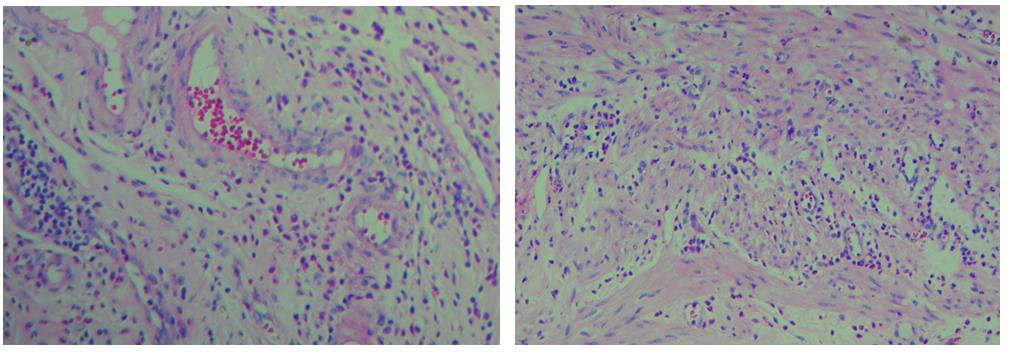

細胞中的細胞核由帶負電荷的酸性物質組成,與帶正電荷的堿性染料蘇木素的氧化物三氧化蘇木紅有較強的親和力;而細胞漿則相反,因含有帶正電荷的堿性物質而與帶負電的酸性染料曙紅Y的親和力較強;細胞或組織切片經(jīng)HE染色后,細胞核被染成藍紫色,細胞漿、紅細胞、肌纖維、膠原纖維、結締組織、嗜伊紅顆粒等被染成不同程度的紅色、粉紅色或橙紅色,與藍色的細胞核形成鮮明的對比,因此更易于觀察細胞或組織中正常成份和病變成份的一般形態(tài)結構。

【實際染色效果】